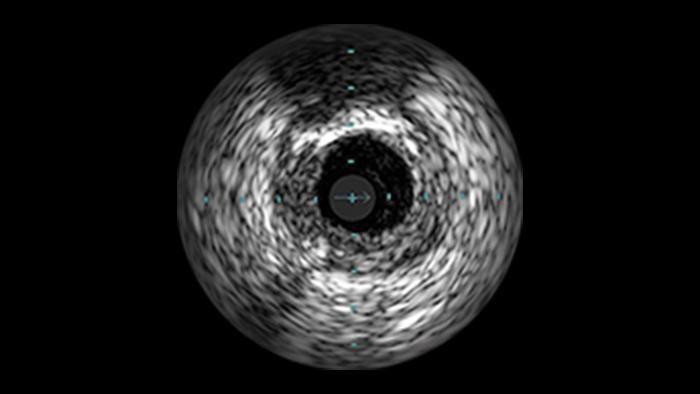

Ultra low contrast PCI

Most cardiac patients fall under the high-risk category for acute kidney injury (AKI)2